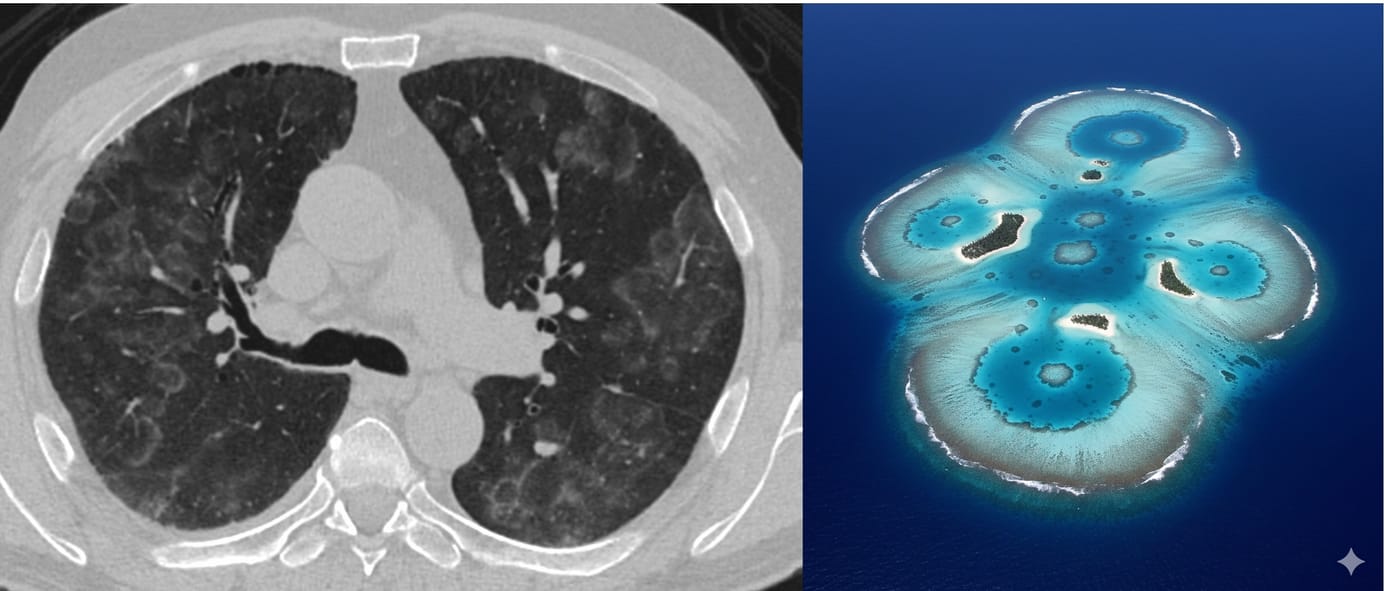

It may be worth mentioning the presence of mucus plugs and whether 4 or more than 4 segments are involved. It does not take much time…maybe 1 minute extra…if you know the patient has asthma.